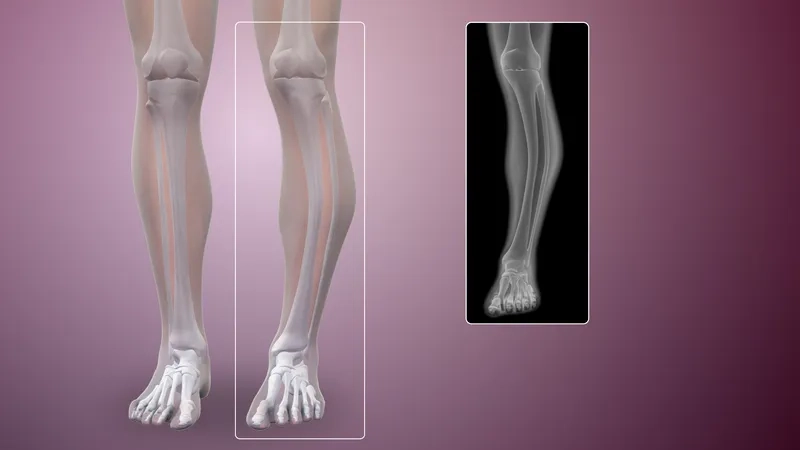

An X-ray showing bone changes from Paget's disease